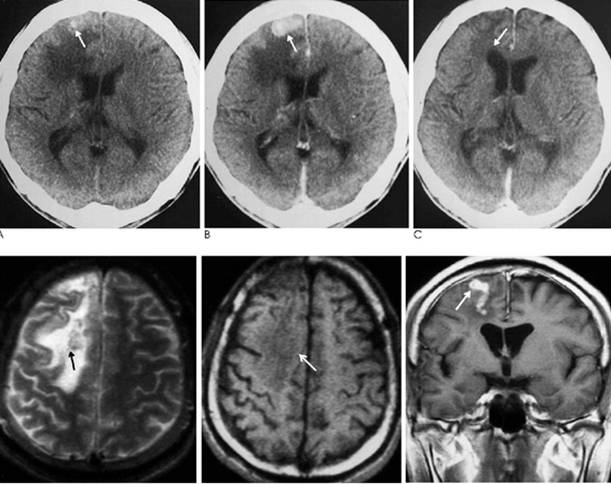

20.Moon W.K., Chang K.H., Cho S.Y., Han M.H., Cha S.H., Chi J.G., et al. Cerebral sparganosis: MR imaging versus CT features. Radiology. 1993;188(3):751-757.

21.Song T., Wang W.-S., Zhou B.-R., Mai W.-W., Li Z.-Z., Guo H.-C., et al. CT and MR characteristics of cerebral sparganosis. AJNR Am. J. Neuroradiol. 2007;28(9):1700-1705.

33.Chang K.H., Cho S.Y., Chi J.G., Kim W.S., Han M.C., Kim C.W., et al. Cerebral sparganosis: CT characteristics. Radiology. 1987;165(2):505-510.

34.Chang K.H., Chi J.G., Cho S.Y., Han M.H., Han D.H., Han M.C. Cerebral sparganosis: analysis of 34 cases with emphasis on CT features. Neuroradiology. 1992;34(1):1

35.Liao H., Li D., Zhou B., Liu J., Li Y., Liu H., et al. Imaging characteristics of cerebral sparganosis with live worms. J. Neuroradiol. J. Neuroradiol. 2016;43(6):378-383.